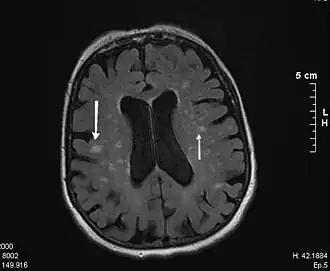

diffuse, samenvloeiende wittestofafwijkingen

Leukoaraiose[1] (Oudgrieks λευκός, "wit"[2] en ἀραίωσις, "verdunning"[2] van ἀραιός, "dun"[2]) is de benaming voor diffuse, confluerende (samenvloeiende) afwijkingen in de witte stof gezien op CT- en MRI-scans van de hersenen.[3] De afwijkingen worden vaak gezien op hogere leeftijd en zijn geassocieerd met vasculaire risicofactoren zoals hoge bloeddruk en hyperhomocysteïnemie.

Leukoaraiose wordt gekenmerkt door diffuse, samenvloeiende wittestofafwijkingen die een verlaagde densiteit (dichtheid) op CT-scans vertonen en op T2-gewogen en FLAIR MRI-opnames een hyperintens signaal geven.